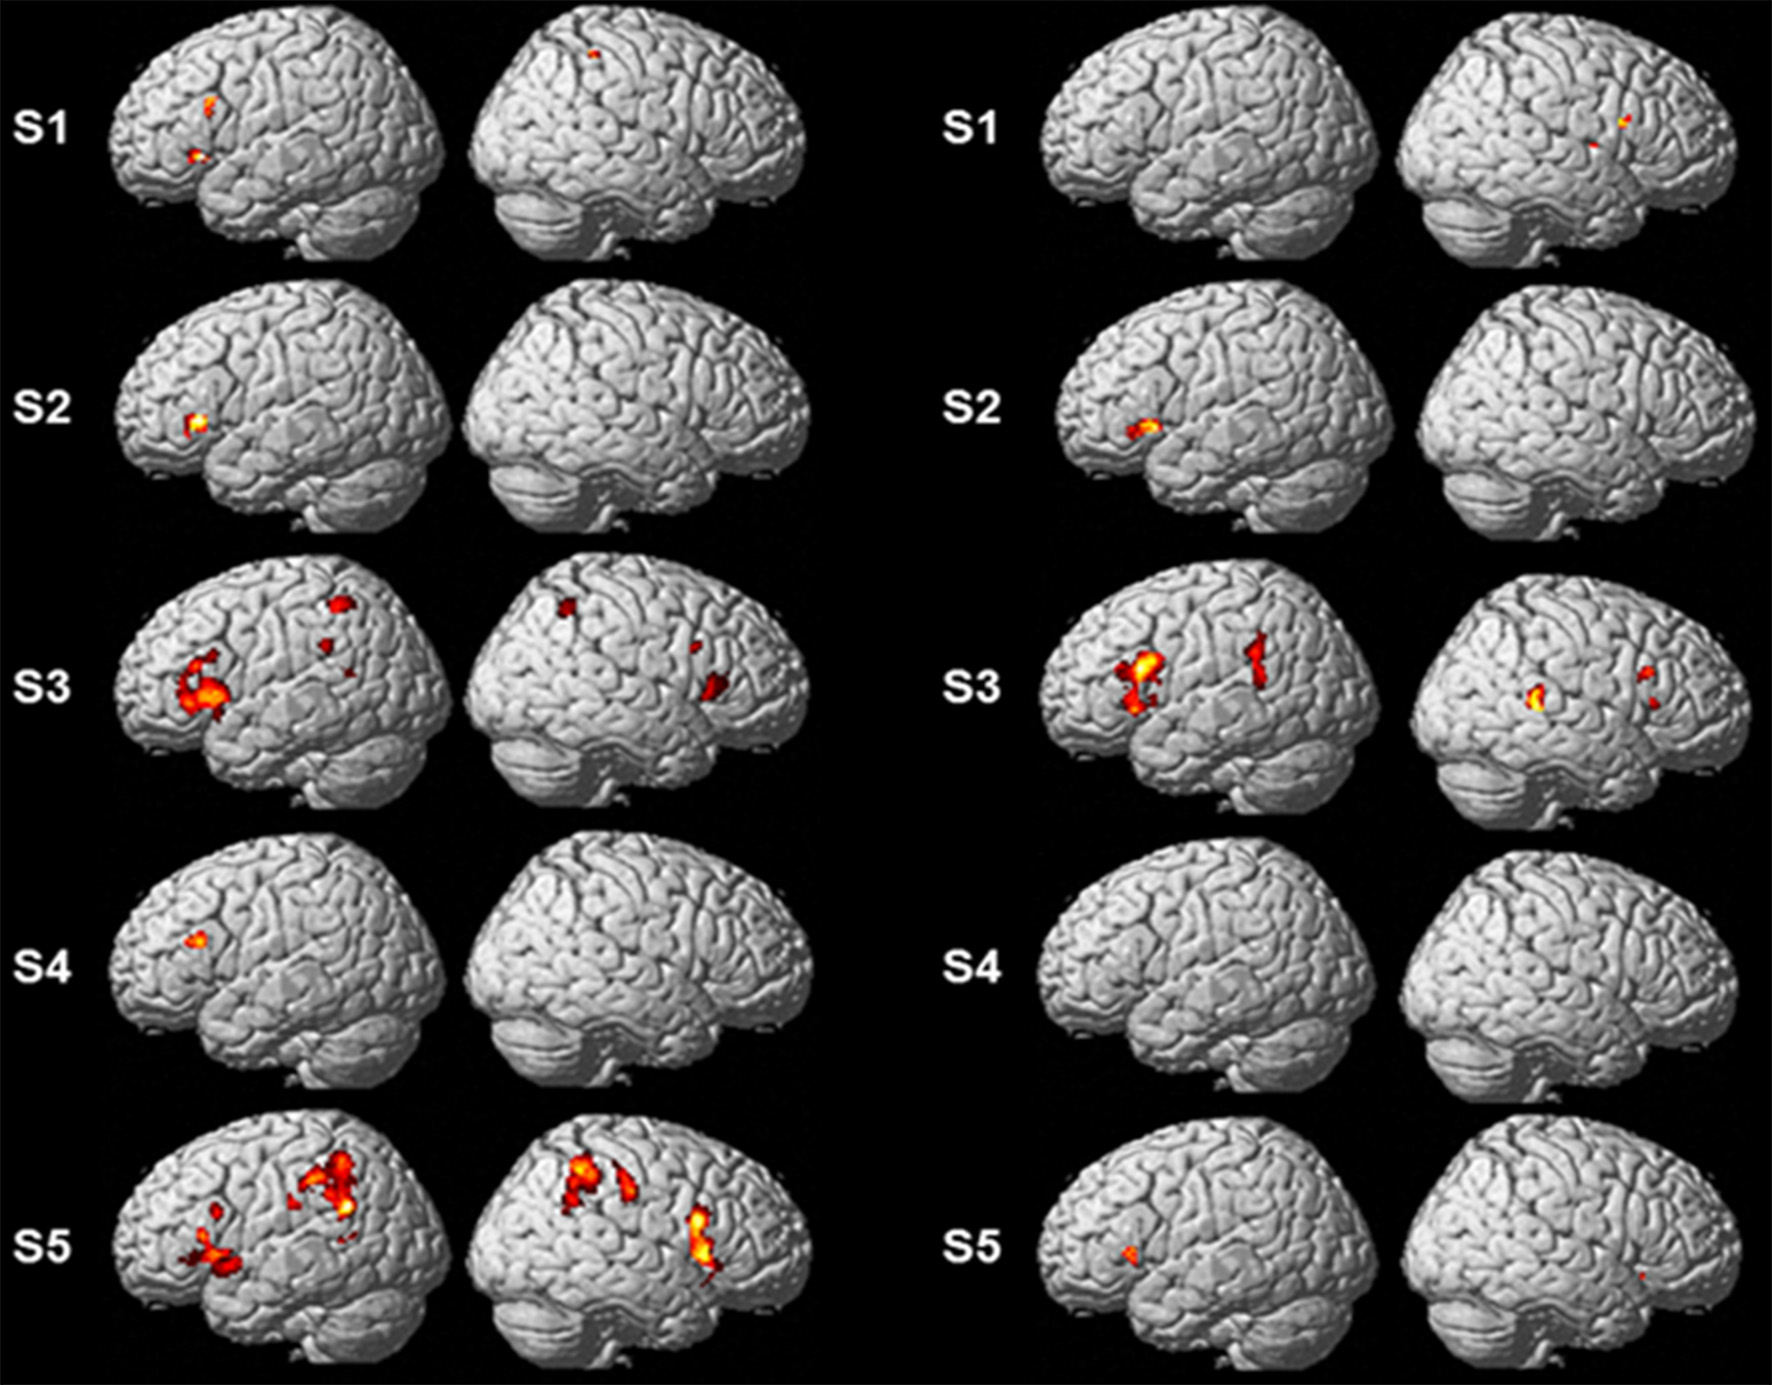

Single-Subject Analyses

Single-subject analyses consistently revealed increased activity in left pars triangularis in all five subjects during backward translation. In addition, during the same condition results revealed a huge inter-individual variability in all other regions of the language-control network (left column of Figures 1, 2 and Table 3). By contrast, during forward translation single-subject analyses did not reveal such a huge overlap across subjects but rather high variability (right column of Figures 1, 2 and Table 4).

Figure 1. Results of the single-subject analyses. Significant results for each subject (S1–S5) are shown on rendering surfaces for both the linear contrasts “translation L2 to L1” vs. “shadowing L2” (left side) and “translation L1 to L2” vs. “shadowing L1” (right side).

Figure 2. Results of the single-subject analyses. Significant results for the linear contrasts “translation L2 to L1” vs. “shadowing L2” (first three rows, S3, S5, S1) and “translation L1 to L2” vs. “shadowing L1” (last four rows, S2–S5) are depicted on transversal (left), coronal (middle), and sagittal (rigth) brain slices. The intersecting planes correpond to the coordinates depicted in Tables 3, 4.